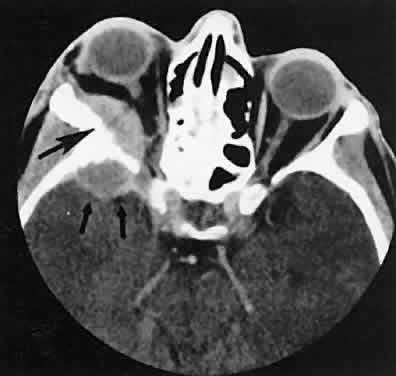

The edema and inflammatory infiltrate that accompany infections are indistinguishable from that associated with orbital inflammations. The presence of sinus disease, however, is a more constant feature with infections, because the sinus represents the infectious nidus in most cases (Fig. 9). In addition to the frequent appearance of sinus disease, the adjacent EOM is invariably enlarged. Less often, orbital infections may be transmitted through the blood, related to a retained foreign body, or spread from the lids. Chandler and colleagues47 classified orbital infections into five groups. Group 1 (preseptal cellulitis) represents inflammatory edema and reflects congestion of venous outflow. Group 2 has actual orbital infiltration/edema with mass effects and functional deficits. Group 3 includes patients with subperiosteal abscesses. Most of these dome-shaped subperiosteal abscesses are located along the medial wall. Group 4 includes patients with orbital abscesses who may display a ring-enhancing lesion with mass effect. Group 5 represents intracranial extension of the inflammation into the cavernous sinus or sinuses, which appear engorged and opacified.

Fig. 9. Orbital cellulitis. A. Axial view shows a subperiosteal soft-tissue mass displacing the medial rectus muscle. The ethmoidal sinus is opacified secondary to inflammatory disease, which invariably precedes the orbital inflammation. B. Coronal view further shows the subperiosteal and ethmoidal sinus inflammation. Inflammation changes also are seen in each maxillary sinus.